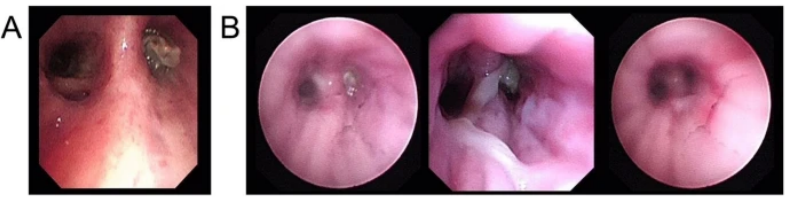

支气管镜在肺真菌病治疗中的应用主要有:①通畅气道:清除气道潴留物,解除机械阻塞。②冲洗引流:脓腔冲洗引流;液性病灶穿刺引流;炎症部位支气管冲洗;导管冲洗;穿刺引流。③局部用药:支气管冲洗、留置导管注药、药物缓释系统置入。病例:一名45岁男性因咳嗽、咳黄痰、呼吸困难持续5个月入院,患者胸部CT提示肿块引起的阻塞性肺不张(图3),但初步病理活检并未明确支持肿瘤诊断。这种不确定性可能与浅表取样有关,但不能完全排除肿瘤病变,使用硬质支气管镜检查缓解气道阻塞。术中见气道内白色肿块,该肿块松散地附着在支气管壁上(图4),镊子取出肿块时出血极少。肿块的组织学检查显示慢性化脓性炎症和肉芽肿形成、提示新型隐球菌感染。通过宏基因组二代测序证实了BALF中新生梭菌的存在。同时,血清隐球菌荚膜抗原检测结果呈阳性,氟康唑抗感染后痊愈。注:A:右主支气管和右中支气管有肿块,右下叶不张;B:右主支气管肿块消失,肺复张;C:右主支气管肿块完全消失和完全肺复张。图源:Medicine (Baltimore), 2024, 103(12):e37455.注:A:硬质支气管镜检查前软性支气管镜检查,显示右侧主支气管有肿块,导致闭塞;B:硬质支气管镜检查3天后软性支气管镜检查,证明成功从右侧主支气管中切除肿块。图源:Medicine (Baltimore), 2024, 103(12):e37455.隐球菌病胸部CT大部分表现为结节影,部分可有实变和坏死。支气管内隐球菌病导致的严重气道阻塞病例罕见,我们认为选择早期呼吸干预是一种理性的选择。首先,近一半的阻塞性支气管内隐球菌病患者对抗真菌药物反应不佳。其次,长期肺不张对肺复张构成挑战,可能导致永久性肺塌陷和肺功能受损,甚至最终导致肺实质感染和纤维化。软性支气管镜检查有助于区分内在性梗阻和外在压迫性,而硬质支气管镜检查可以更好地了解内在性梗阻性病变的性质,并提供一种气管内治疗手段。毛霉菌极易堵塞局部血管和支气管,病灶药物浓度低,单纯的全身药物治疗效果并不理想。近年来的研究发现两性霉素B局部给药,在抗真菌治疗方面会起到一定的辅助作用,包括雾化吸入、鞘内注射等,经支气管镜应用两性霉素B局部灌注对肺毛霉病可取得良好的效果。对于支气管被毛霉的菌丝体阻塞的患者,采用积极的介入治疗也可取得一定的效果,但应小心谨慎,防止出现大出血。各种介入治疗方法,包括两性霉素B局部灌注、冷冻治疗等,获得了不错的疗效。肺毛霉病的介入治疗必须具备全身麻醉、气管插管、预置球囊及有经验的呼吸内镜介入团队等。冷冻治疗建议在全麻气管插管方式下实施,出血风险高的患者还需要预置止血球囊。研究报道,10例肺毛霉病介入治疗患者均临床治愈,死亡0例。10例患者中应用冷冻探头冻取病灶8例,活检钳钳除病灶7例,套器套治疗2例,异物钳钳取病灶2例。介入和治疗经支气管镜直接局部灌注同步进行,1次/周,共1~6次。冷冻治疗的过程中3例患者预置球囊防止支气管内出血。10例患者中4级出血1例,3级出血2例,2级出血4例,3例患者无出血。支气管内出血均在5~10 min停止,术后少量痰中带血3~4天,术后气胸0例。牟向东教授团队在应用全身+局部治疗肺毛霉病的同时联合气管镜下介入技术清除阻塞气道和血管脓栓,并且在导航和超声定位下局部精准灌注两性霉素B,提高了肺组织内的药物浓度,降低了全身用药带来不良反应的概率,获得了显著的临床疗效,灌注后患者亦无明显不良反应(图5-图8)。注:右肺中叶和右肺下叶内基底段可见多发斑片影和片状肺内渗出实变影(箭头所示)。图源:https://www.btch.edu.cn/tszl/zbzx/fzjbzzzx/zb15blfx/91912.htm注:病理显示坏死组织内大量毛霉菌丝,并可见菌丝侵袭血管。